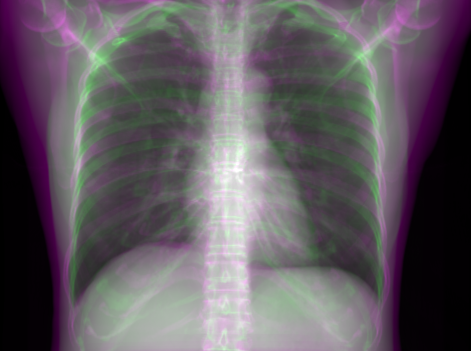

5.1 Chest Data

Refer to caption

(a) Reference

(b) 0superscript00^{\circ} perspective

(c) (b)-(a)

0.4237, -, -

0.4002, 17.01, 0.6532

Pix2pixGAN

(d) 0superscript00^{\circ} Cartesian

(e) 0&180superscript0superscript1800^{\circ}\&180^{\circ} Cartesian

(f) 0&180superscript0superscript1800^{\circ}\&180^{\circ} polar

0.4303, 7.08, 0.8535

0.4214, 5.37, 0.9098

0.4240, 3.83, 0.9536

(g) (d)-(a)

(h) (e)-(a)

(i) (f)-(a)

TransU-Net

(j) 0superscript00^{\circ} Cartesian

(k) 0&180superscript0superscript1800^{\circ}\&180^{\circ} Cartesian

(l) 0&180superscript0superscript1800^{\circ}\&180^{\circ} polar

0.4272, 10.92, 0.8222

0.4281, 9.37, 0.8424

0.4248, 8.12, 0.8859

(m) (j)-(a)

(n) (k)-(a)

(o) (l)-(a)

Figure 10: Perspective deformation learning in one exemplary patient case for chest X-ray imaging. The maximal horizontal cardiac diameter and the maximal horizontal thoracic diameter in (b) and (d)-(f) are indicated by the horizontal red lines, while those in the reference image (a) are green lines. The cardiothoracic ratio, RMSE, and SSIM for each image is displayed in its corresponding subcaption.

The results of one patient in chest X-ray imaging are displayed in Fig. 10, where the cardiothoracic ratio is assessed as an exemplary clinical application [32]. In the reference image (Fig. 10(a)), the maximal horizontal cardiac diameter (MHCD) and the maximal horizontal thoracic diameter (MHTD) are indicated by two green horizontal lines. Its cardiothoracic ratio is 0.4237. In the 0superscript00^{\circ} perspective projection image (Fig. 10(b)), all the anatomical structures can be visualized with fine resolution. However, due to perspective deformation, anatomical structures, e.g. the ribs and the spine, are deformed. The deformations are visualized better in the difference image Fig. 10(c). Compared with the ribs and the spine, the heart has less deformation as its location is closer to the isocenter. In Fig. 10(b), the MHCD and the MHTD are indicated by two red horizontal lines, while the green lines are those of the reference image. While the MHCD has changed little from 10.47 cm to 10.16 cm, the MHTD has changed considerably from 24.71 cm to 25.40 cm. As a consequence, the cardiothoracic ratio becomes 0.4002, which is below the normal range of 0.42 - 0.50 [32]. The result of learning perspective deformation from 0superscript00^{\circ} single view is displayed in Fig. 10(d), where the MHCD and the MHTD are 10.63 cm and 24.71 cm, respectively. The MHTD of Fig. 10(d) is the same as that of the reference image. This is also reflected by the difference image Fig. 10(g), where the lower ribs have small errors. However, the upper ribs as well as the spine still have considerable errors. The results of perspective deformation learning from 0&180superscript0superscript1800^{\circ}\&180^{\circ} views in Cartesian and polar coordinates are displayed in Fig. 10(e) and Fig. 10(f), respectively. The measured MHCDs and MHTDs in these two images are very close to the reference ones. Hence, their cardiothoracic ratios, 0.4214 and 0.4240 respectively, are close to the reference ratio as well. In the difference images (Fig. 10(h) and Fig. 10(i)), the errors of ribs and spine decrease as their boundaries are no longer apparently visible. Nevertheless, Fig. 10(i) has less error than Fig. 10(h), achieving the smallest RMSE value of 3.83. The quantitative evaluation of all the 162 testing datasets is displayed in Tab. II, where learning perspective deformation from two complementary views in polar coordinates achieves the least RMSE 4.98 and highest SSIM 0.9517, demonstrating the superiority of learning perspective deformation from two complementary views in polar coordinates.

The TransU-Net results are displayed in Figs. 10(j)-(l). Compared with their corresponding Pix2pixGAN results, the TransU-Net prediction images are more blurry, although the same perceptual loss is used. The error images in Figs. 10(m)-(o) indicate that TransU-Net reduces perspective deformation better with complementary views than a single view. The quantitative evaluation in Tab. II shows that TransU-Net cannot effectively reduce perspective deformation with a single view. With complementary views in both Cartesian and polar coordinate systems, TransU-Net achieves comparable performance, which is still considerably worse than that of Pix2pixGAN. The inferior performance of TransU-Net to Pix2pixGAN on the chest data is potentially caused by the repetitive nature of the segmental rib anatomy, which leads TransU-Net to be ineffective in extracting position-dependent features.